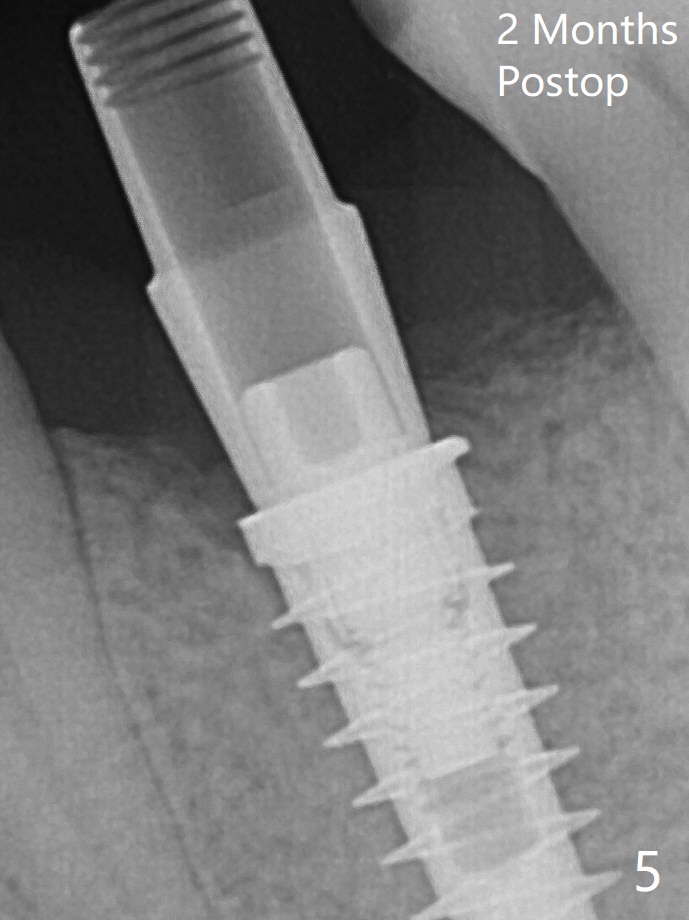

放置基台前,骨粉放置低于植体上端(Plateau),但是远中仍有间隙(图二箭头)。 放置基台后,两度填骨粉(图三*),远中间隙仿佛消失(箭头)。术后两个月,植体顶端似乎被牙槽嵴覆盖了(图五)。